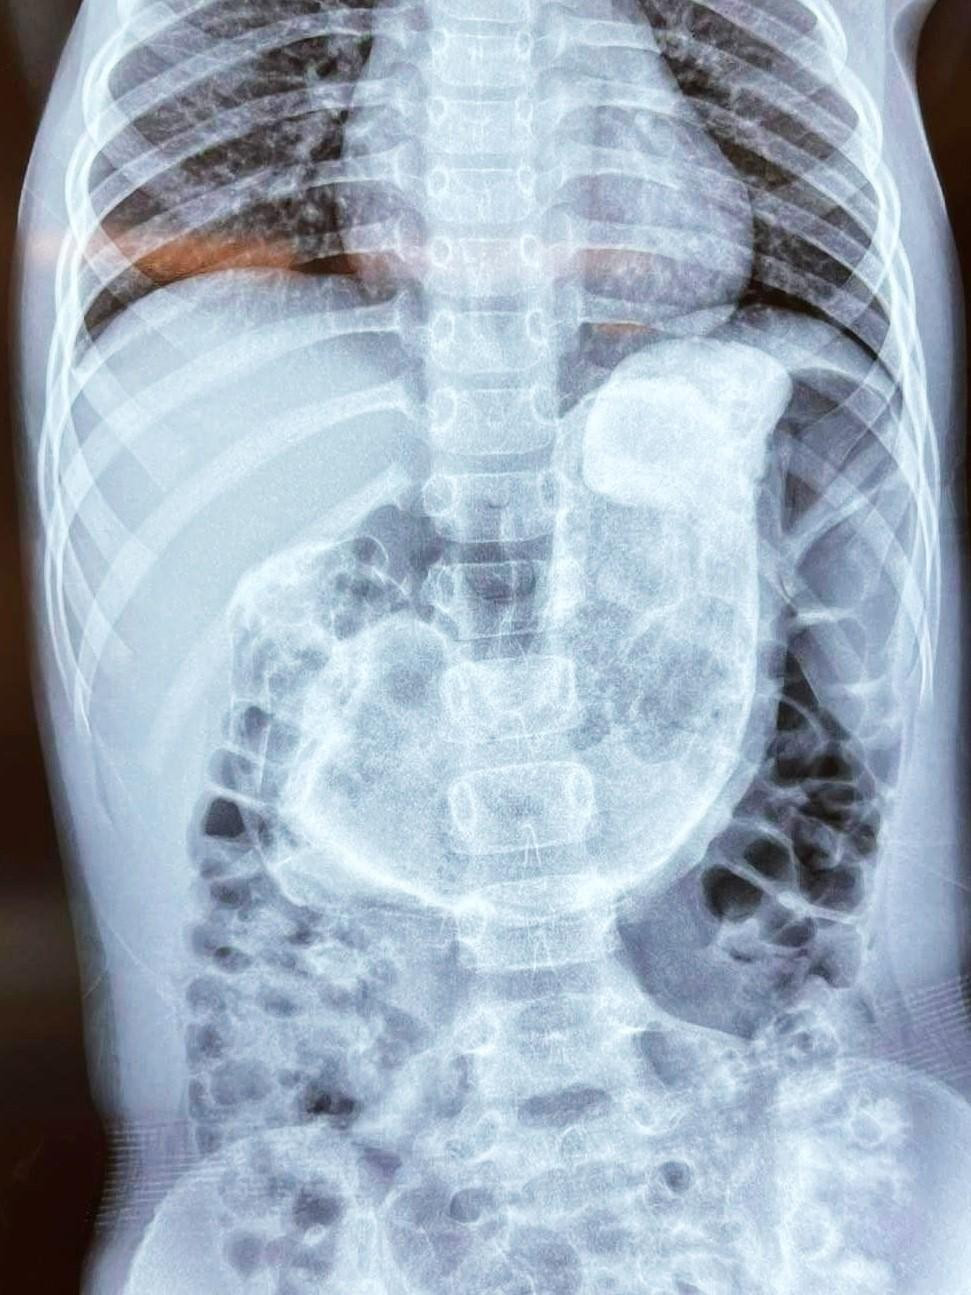

| Búi tóc lớn (vùng màu trắng ở giữa) gần như chiếm trọn dạ dày của bệnh nhi |

Nghi ngờ bé đã tự bứt tóc của mình để ăn, các bác sĩ tiến hành kiểm tra hình ảnh thì phát hiện một búi tóc rất lớn đã gây tắc gần như hoàn toàn đường tiêu hóa của bệnh nhi. Ngay lập tức, trẻ được chỉ định thực hiện phẫu thuật để ngăn chặn nguy cơ nhiễm trùng, hoại tử đường ruột.

BS Tạ Huy Cần, Trưởng khoa Ngoại Tổng hợp cho biết, trong quá trình phẫu thuật ghi nhận, búi tóc rất lớn, trọng lượng khoảng 1kg đã chiếm trọn lòng dạ dày bệnh nhi. Búi tóc siết chặt và căng phồng niêm mạc, nguy cơ gây thủng dạ dày, tắc ruột, nhiễm trùng, nhiễm độc toàn thân. Ê kíp phẫu thuật đã lấy thành công búi tóc ra ngoài, giúp bé vượt qua nguy kịch.